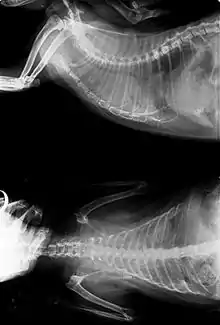

Cancer can be detected at an early stage by observing certain signs and symptoms. Common diagnostic methods include physical examination, x-rays, ultrasounds, cytology, blood tests, urine tests, and nuclear scans. Depending on the type of cancer and its level of progress, surgery, radiation, chemotherapy, or immunotherapy may be used to treat the cancer. Although research into causes and treatment of feline cancers has been slow, there have been advances in radiation therapy, as well as newer and improved chemotherapy procedures.[2]

- X-rays are divided by two types: plain film and constrat techniques. They are commonly used to identify tumors of the lung, gastrointestinal tract and bladder.